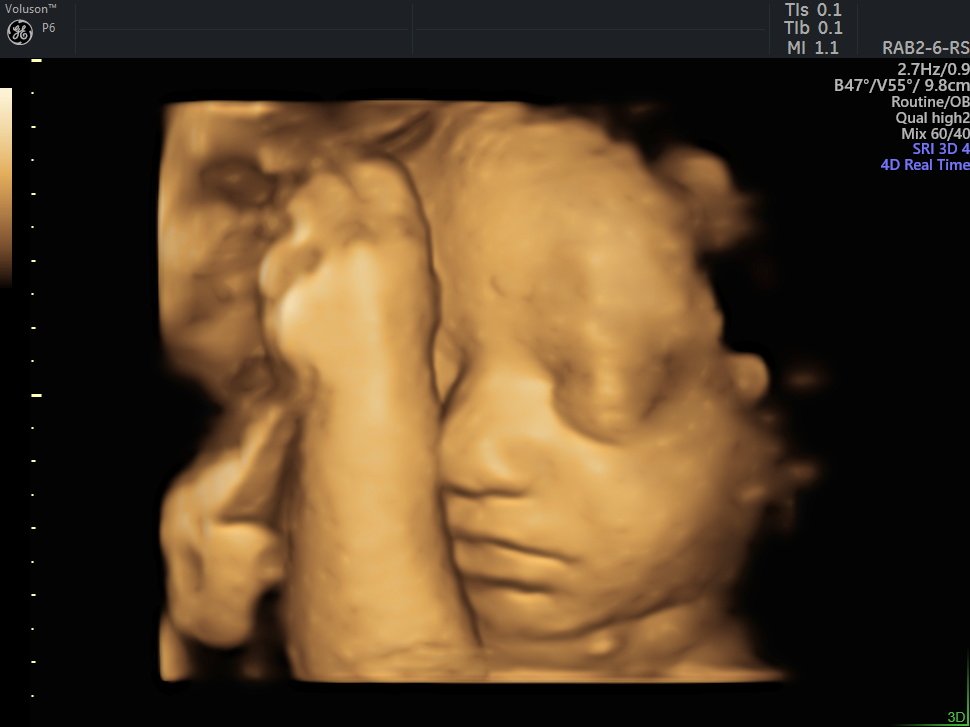

4 Boyutlu (Renkli) Ultrason ve Doppler Ultrasonografi

4 D Ultrasonografi